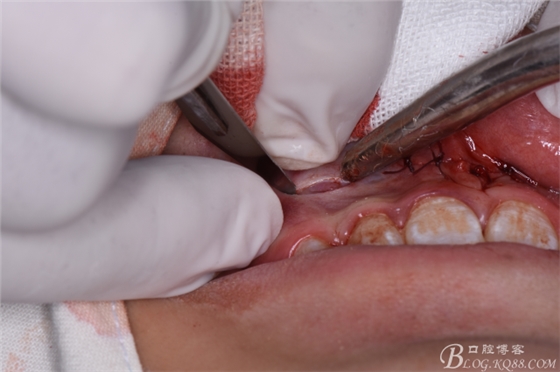

圖23.去骨、暴露出鼻底下方的倒置多生牙。

圖24.將多生牙分成牙冠和牙根兩部分,分別拔除。

圖25.拔除后??p合完成的雙切口。